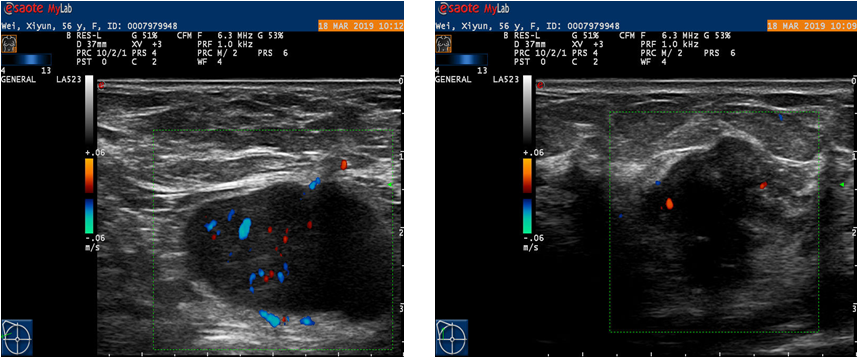

右侧乳腺见一22*19*18mm低回声,BI-RADS 5类,右侧腋下I区淋巴结,4C